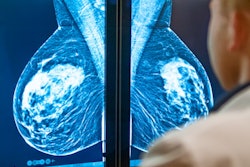

Artificial intelligence (AI) has been touted as having much potential to help radiologists interpret mammography images. But AI still needs to clear some hurdles before being more widely accepted in screening mammography -- as well as by patients, according to Dr. Emily Conant.

Despite the challenges, AI has opportunities to improve accuracy, decrease variability in interpreting breast images, and improve efficiency in delivery of care, especially as more studies are published, Conant said.